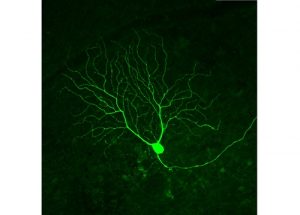

Mehr erfahren zu: "Netzhautchip bei trockener AMD: Bonn und Ludwigshafen melden ihre ersten Implantationen" Netzhautchip bei trockener AMD: Bonn und Ludwigshafen melden ihre ersten Implantationen Bonn ist das erste deutsche Universitätsklinikum, an dem die Implantation eines neuen bionischen Netzhautimplantates zur Verbesserung der Sehfunktion bei trockener altersabhängiger Makuladegeneration (AMD) vorgenommen wurde. Operateur war Klinikdirektor Prof. Frank […]

Mehr erfahren zu: "AMD-Therapie: Volker-Homann-Stiftung fördert zwei Projekte an der Universitäts-Augenklinik Freiburg" AMD-Therapie: Volker-Homann-Stiftung fördert zwei Projekte an der Universitäts-Augenklinik Freiburg Die Volker-Homann-Stiftung unterstützt zwei Projekte der Klinik für Augenheilkunde des Universitätsklinikums Freiburg zur Erforschung neuer Therapien der altersabhängigen Makuladegeneration (AMD).